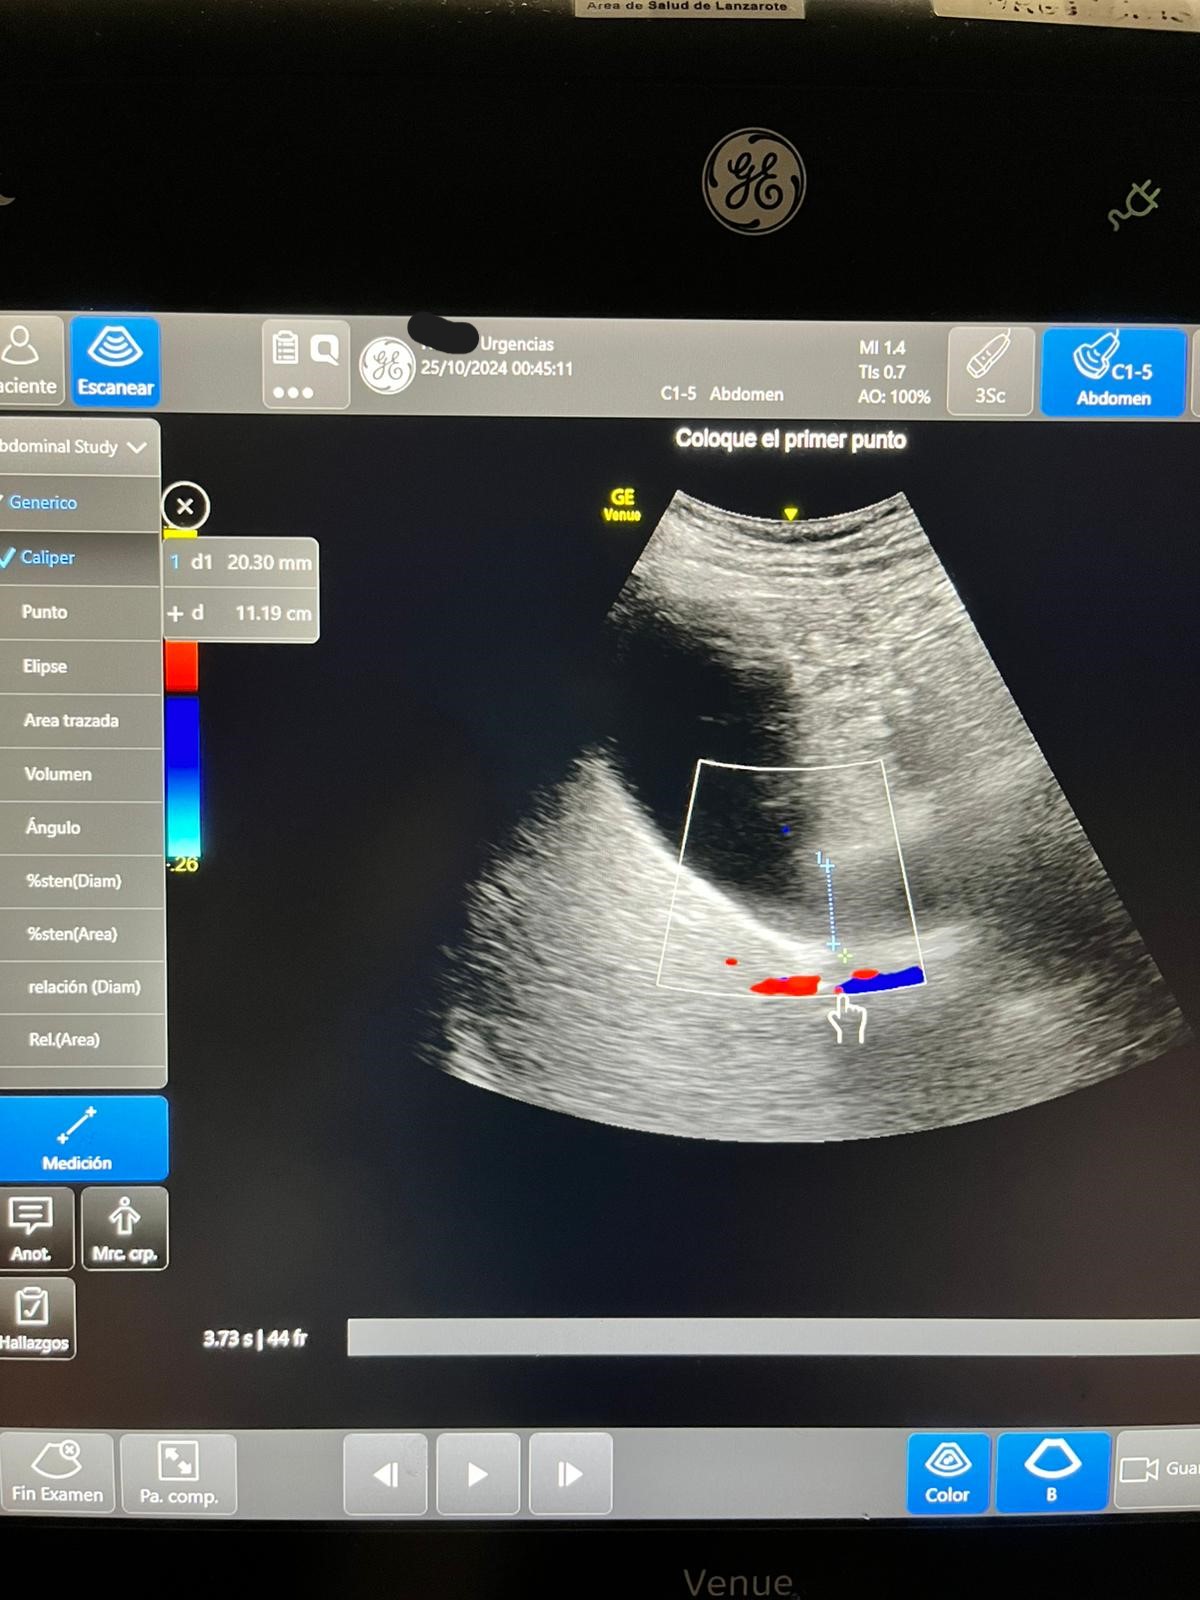

Ecografía: hígado y vías biliares normales sin formaciones expansivas. Coledoco de calibre normal.

Vesícula biliar distendida con litiasis múltiple suncentimétricas y barro biliar de paredes finas.

Páncreas y bazo sin alteraciones Riñones normales, sin dilatación de sistema excretor, urolitiasis ni lesiones expansivas sólidas. Quistes corticales simples en ambos riñones en tercio medio del izquierdo quiste complejo con tabiques finos y calcificación.

JC: coledocolitiasis DxD: IAM, cólico biliar.